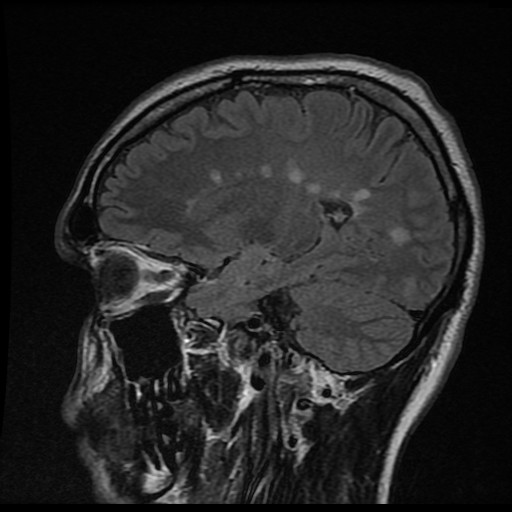

Hallazgo de lesiones en resonancia magnética

Un hallazgo en la resonancia magnética nunca debe interpretarse de forma aislada: siempre hay que valorarlo en el contexto clínico del paciente.